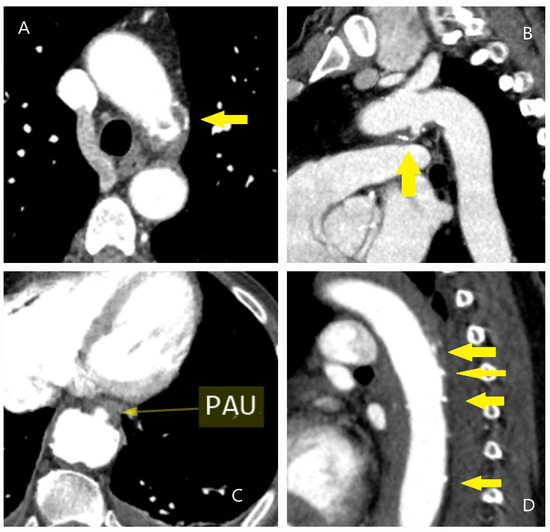

4.1. Dissection, Intramural Hematoma, and Penetrating Aortic Ulcer